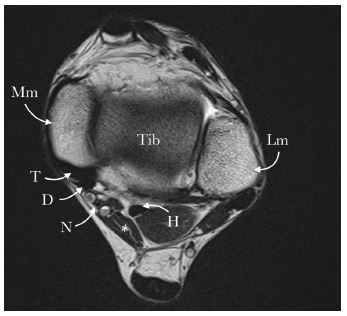

MRI of the left ankle showed borderline thickening of the Achilles tendon measuring 6mm with minor high signal in the Kager’s fat pad. There was a prominent FDAL (Flexor Digitorum Accessorius Longus) accessory muscle in the tarsal tunnel resulting in crowding on the neurovascular bundle (Figure 1). The rest of the tendons and ligaments of the joint looked unremarkable.

Figure 1: Axial T2 W image of the left ankle showing an FDAL muscle (*) with crowding of the tarsal tunnel.

Mm: Medical malleolus; Lm: Lateral malleolus; Tib: Tibia; T: Tibialis posterior tendon; D: Flexor digitorum longus tendon; N: neurovascular bundle of posterior tibial vessels and tibial nerve; H: Flexor hallicus longus tendon